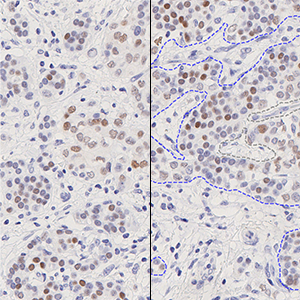

Outlines of identified invasive tissue. Nuclei will be detected and classified inside these regions.

Nuclei within the invasive tissue are detected and classified based on their staining as positive or negative nuclei.